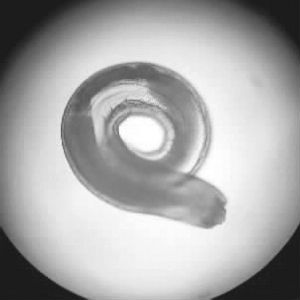

显微镜下的颚口线虫。

颚口线虫在皮肤下的游走路径。